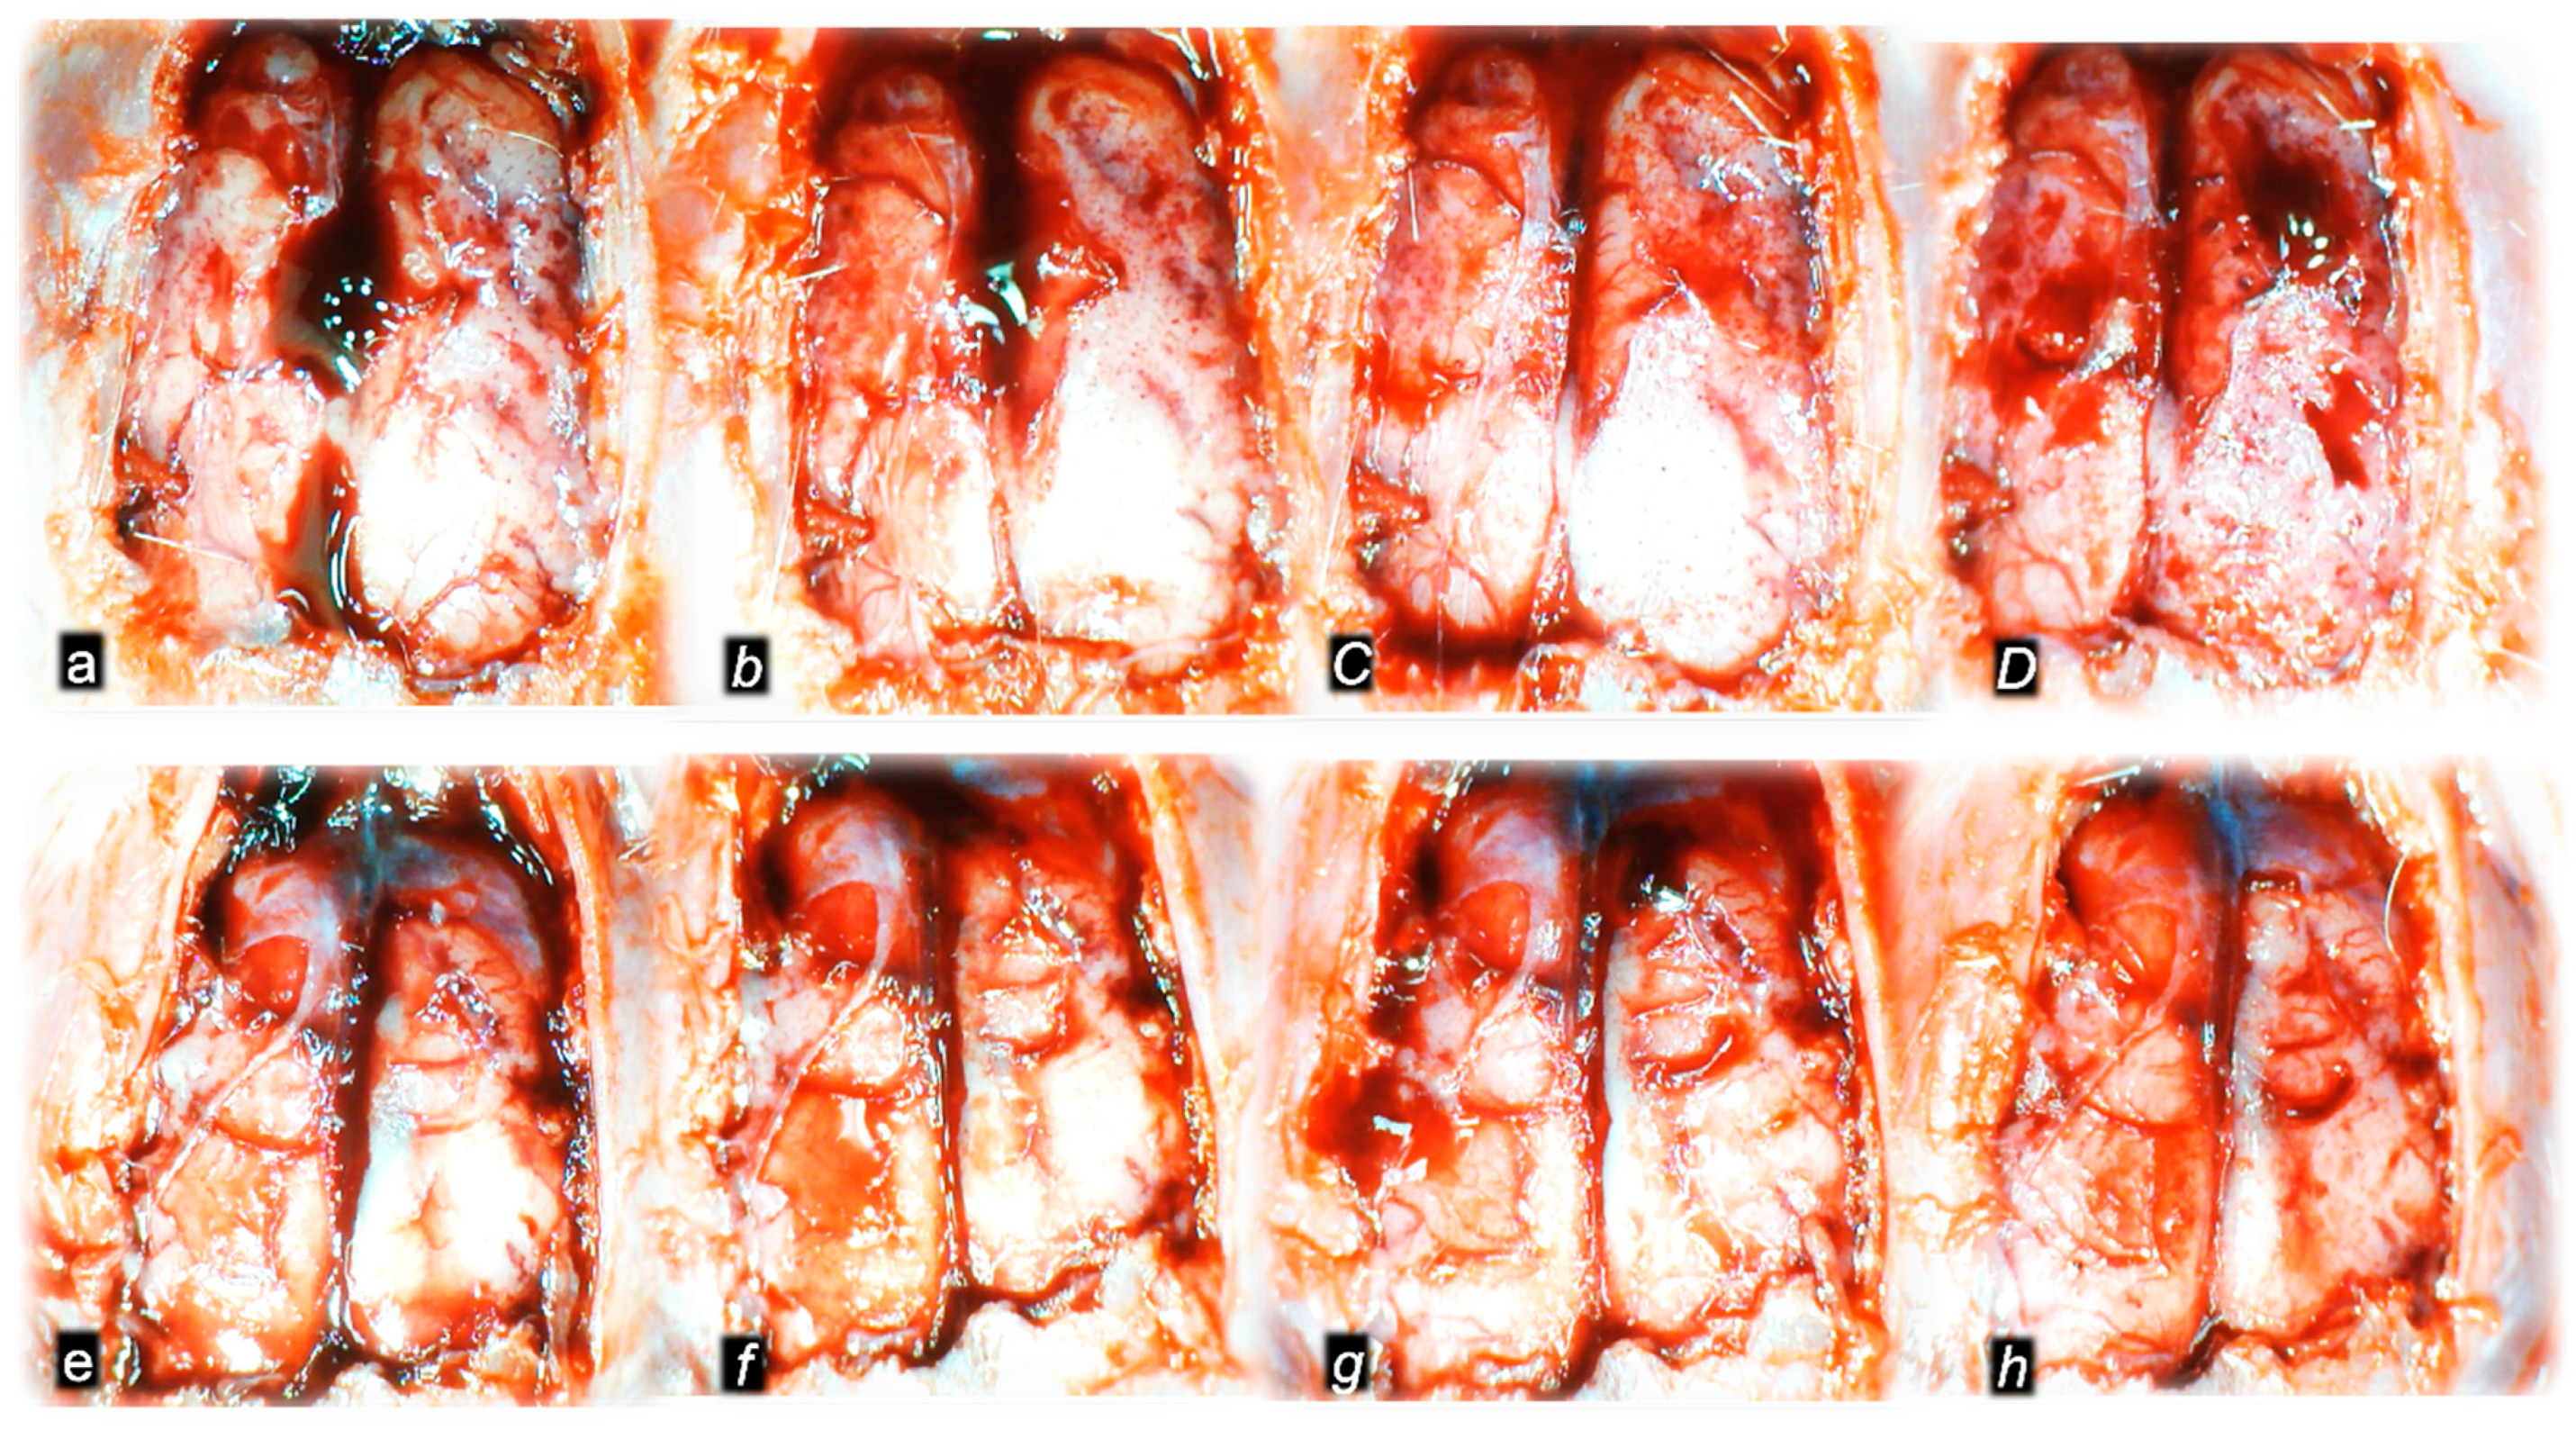

Figure 10.

Gross brain presentation in healthy rats (normal small letters) and then after laureate application into inferior caval vein (italic letters), and subsequent application of the BPC 157 therapy (capital italic letters) or saline (small italic letters) (a–h). Brain presentation in normal healthy rats (a,e), brain swelling presentation immediately upon laurate application (b,f). Then, there was the opposite effect of therapy: decreased brain swelling immediately upon BPC 157 administration (C), decreased brain swelling in BPC 157-treated rats immediately before sacrifice (D), in contrast to further brain swelling immediately upon saline administration (g) and increased brain swelling in saline-treated rats immediately before sacrifice (h). A similar presentation was noted with both intragastric and intraperitoneal BPC 157 therapy.

The consistent outcome is that the presentation of these vessels (Figure 3 and Figure 4) and the heart (Figure 5) returns to close to normal vessel and heart presentation and close to normal functioning to re-establish blood flow (multiorgan lesions are largely attenuated) due to BPC 157 therapy. As further support, BPC 157 therapy induced a considerable change toward normal brain presentation and negative pressure values (Table 1 and Table 2) (i.e., brain swelling occurred with the increased intracranial (superior sagittal sinus) hypertension and increased volume (associated with considerable brain injuries) due to the laurate injection, which was reversed by BPC 157 (Figure 5).

Indicatively, as a common clue that might be the cause of failure (i.e., intracranial (superior sagittal sinus), portal, caval hypertension, aortal hypotension, progressed thrombosis, peripherally and centrally, failed collateral recruitment, disturbed ECG presentation, peripheral organs lesion) without therapy, all of the laurate-injected rats converged to display similar brain lesions as well. Moreover, this might be a very rapid effect, as seen with the comparative presentation of the brain before laurate application in naive rats, the immediate severe brain swelling upon laurate application, and rapid counteraction immediately upon BPC 157 therapy application (Figure 10). Since the immediate post-application period, there was observable gross brain swelling (Table 2, Figure 10) and increased intracranial (superior sagittal sinus) hypertension (and portal and caval hypertension and aortal hypotension) (Table 1). Microscopically, severe brain edema and congestion as well as large intracerebral hemorrhage in the frontoparietal area consistently occurred (Table 5, Figure 11, Figure 12 and Figure 13). Notably, there is a rapid therapeutic effect observed after BPC 157 application. BPC 157 therapy reduced intracranial (superior sagittal sinus) hypertension and aortal hypotension, and eliminated portal and caval hypertension; additionally, BPC 157 therapy counteracted brain swelling, concurred with only mild brain edema and congestion, lesser brain hemorrhage, and no intraventricular hemorrhage.